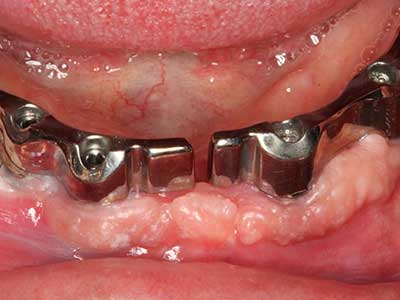

Come dimostrato in passato, pressoché qualsiasi procedura chirurgica che interessa il tessuto osseo rappresenta una possibile indicazione per la piezochirurgia. Quindi, per la preparazione del segmento mobile nella distrazione osteogenetica (figg. 23-25) e nell'osteotomia con tecnica a sandwich si utilizzano appositi raccordi per non danneggiare l'apporto sanguigno alla sezione della cresta, elemento essenziale per la corretta esecuzione di entrambe le tecniche (Gonzalez-Garcia, Diniz-Freitas et al. 2008).

Per la rimozione di un impianto, è possibile preparare una copertura dell'osso vestibolare da sostituire dopo la rimozione della vite dell'impianto, per conservare il contorno della cresta alveolare.